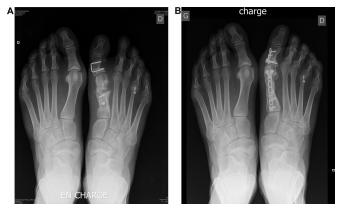

术后即出现拇指内翻,说明内侧关节囊重叠缝合过度,跖骨力线不良引起,通常是关节囊处过度紧缩或是外侧过度松解的结果,可采取踇趾向外位加强包扎8周的方法进行纠正。如果拇内翻仍存在,可能是IMA纠正过度,需再次行跖骨截骨术或跖楔关节融合术,需要尽早做,以减少软组织挛缩导致的相关问题。

B. 跖骨翻修截骨术

由第一跖骨的畸形引发的拇内翻,是单纯肌腱手术纠正拇内翻的禁忌症。纠正跖骨力线异常需要截骨,并一定要联合应用肌腱转位术。